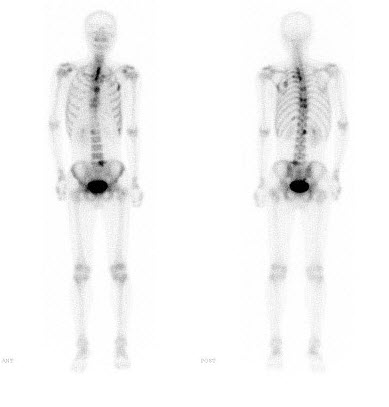

125、单项选择题

男,48岁,肺小细胞癌化疗中,诉全身疼痛,行全身骨显像如图,可能的诊断是()

A.广泛骨转移瘤

B.颅骨有冷区

C.大致正常的影像

D.颅骨有“甜面圈”征

E.是超级骨显像